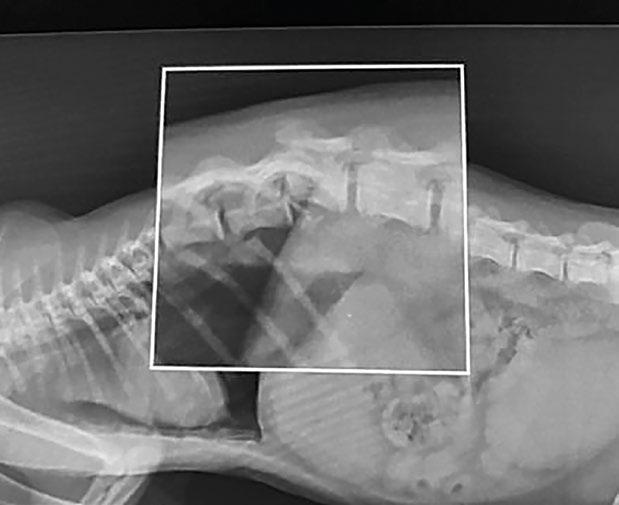

Las proyecciones de tórax incluyen: ventrodorsal, dorsoventral y lateral (figura 1). Es importante extender bien las extremidades anteriores para evitar superposiciones de estructuras. Por norma general, para un buen estudio radiográfico se solicitan tres proyecciones de tórax (LLD, LLI y VD o DV). De este modo podemos evaluar la silueta cardiaca, el estado del pulmón de forma bilateral y la circulación en su totalidad. En algunas patologías como las masas pulmonares, se puede ver esa imagen con claridad en una proyección lateral y en la contraria no verlo por superposición de estructuras. En pacientes con respiración comprometida se debe realizar la proyección que menor dificultad respiratoria le genere, preferiblemente bajo sedación para evitar el estrés, y si se

puede elegir, una proyección dorsoventral o ventrodorsal (figura 2).

Figura 3. Proyección lateral de abdomen. Dilatacióntorsión de estómago. Figura 1. Proyección lateral de tórax. Neumotórax. Figura 2. Proyección ventrodorsal de tórax. Metástasis pulmonar.